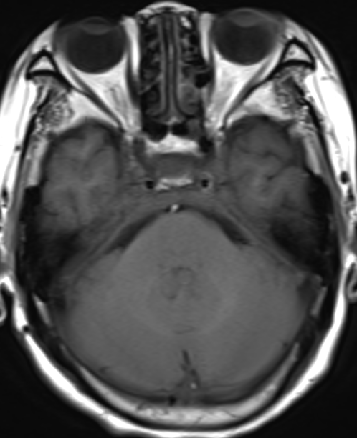

2013-5-16 MRI